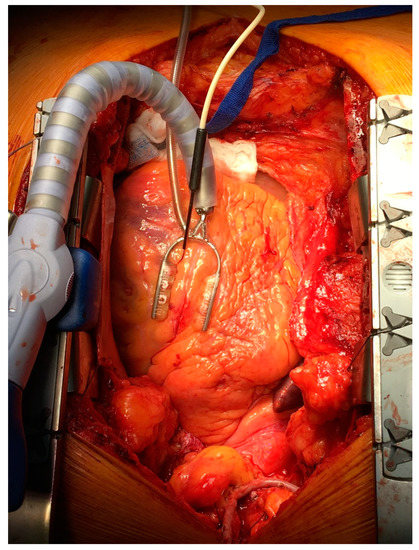

All measurements of myocardial microvascular perfusion were carried out using laser Doppler flowmetry (Periflux System 5000, Perimed, Järfälla, Sweden) equipped with the special insertion probe (Stainless Steel Probe 411-311, Perimed, Järfälla, Sweden). Laser Doppler intramuscular fiber-optic perfusion probe (Figure 1) was inserted 3–5 mm into the myocardium during beating heart surgery downstream from the planned anastomosis (Figure 2). After clamping and incision of coronary artery, an anastomosis was performed with prepared graft. When anastomosis was completed, clamps were taken off and the flow through the coronary artery was restored. All measurements were carried out continuously during the operation. Baseline registration was performed for approximately 3 min. Then, the perfusion measurements were continued during vascular anastomosis and approximately 3 min after occlusion release. At the end, the needle probe was removed from the myocardium and subsequently the next anastomosis was performed.

Figure 1. Laser Doppler intramuscular fiber-optic perfusion probe.

Figure 2. Laser Doppler intramuscular fiber-optic perfusion probe was inserted into the myocardium during beating heart surgery downstream from the planned anastomosis.